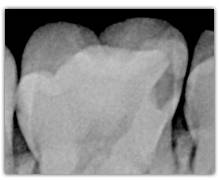

What represent the white, blue, red or black areas which can been seen on the tooth?

According to the pathologies of the tooth (destructured enamel, affected dentine, anfractuous fissure, presence of a crown…), the signal of fluorescence of the dentine will be different (weaker, darker, redder, absent…)

The spectrum of the signal of fluorescence (let’s call it "its color") is rather in the green when the dentine is healthy and red/dark when the dentine is infected.